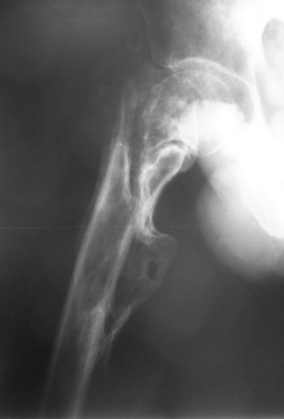

Больной Н. 44 года травма 1,5 года назад июнь 2008 года чрез-под вертельный перелом правого бедра. Во время лечения у больного развился алк. делирий, проводилось консервативное лечение перелома.

Беспокоят боли, укорочение конечности.Укорочение 3 см. Ногу поднимает, сгибание ограничено, ротационные движения в полном объеме.На КТ перелом сросся за счет костной мозоли.Что делать?

Уважаемый Глеб, боли из-за ложного сустава шейки бедра. Сращения там нет.

Уважаемый Глеб! Укорочение наверное побольше, да и наружно-ротационная установка скорее всего присутствует. Суставная щель прекрасная, головка живее всех живых. Ратую за подвертельную с латерализацией: исключает нарушение механической оси («исключает вальгус в коленe»), максимально удлиняет без натяжения m.iliacus. Для иллюстрации остеотомия-переделка (слава богу не автопеределка) у мужчины 65 лет.